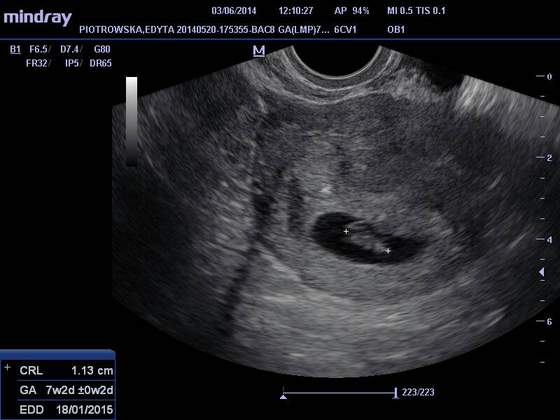

Wizyty, usg, zdjęcia itp

witam jestem po wizycie krwiaka mnie ma wyniki super cytologia piękna dzidzia wierzga jak szalona aż miło było popatrzeć oto zdjęcie